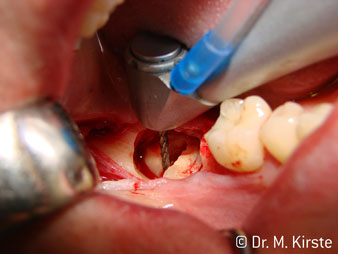

Le contre-angle avec tête angulée à 45° a surtout été choisi pour ses nombreux avantages. Les collègues qui exercent en chirurgie, et à qui cet instrument est principalement destiné, apprécieront très vite la possibilité de travailler efficacement dans des zones très étroites. En particulier, lors d’extractions de dent de sagesse (Ill. 2), où il n'y a pas besoin d’un grand angle d’écartement des tissus mous dans la région de la joue (Ill. 3). Pendant la préparation, une légère rotation de la tête de l’instrument permet un travail rapide et sans risque dans la zone rétromolaire.

La conception particulière des roulements à l'intérieur de la tête du contre-angle garantit un fonctionnement silencieux de l’instrument rotatif et lui procure une grande efficacité de coupe, sans à-coup ; ce qui est appréciable lors des interventions chirurgicales comme par exemple les séparations dentaires et résections apicales (Ill. 4-9).

Le contre-angle avec tête angulée à 45° est très agréable à utiliser. D’emblée on remarque que la partie travaillante de la tête imite l'angle de l’index et qu’ainsi le mouvement que vous souhaitez faire est simplement déplacé de deux ou trois centimètres, parallèlement à la pointe de l’instrument rotatif.“ (Ill. 1)